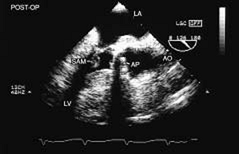

FIGURE 5.45. Porcine aortic prosthesis: hypertrophic cardiomyopathy. In this patient, systolic anterior motion (SAM) of the mitral valve developed after porcine aortic valve replacement for aortic stenosis, which had masked coexisting hypertrophic cardiomyopathy. Note that the left ventricular outflow tract (LVOT) is narrowed to <20 mm in this patient. AO, aorta; AP, aortic prosthesis; LA, left atrium; LV, left ventricle. |

|